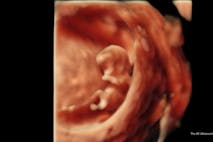

Have you ever wanted to share the miracle of human development with little ones? Live Action is proud to present the "Baby Olivia" board book, which presents the content of Live Action's "Baby Olivia" fetal development video in a fun, new format. It's perfect for helping little minds understand the complex and beautiful process of human development in the womb.